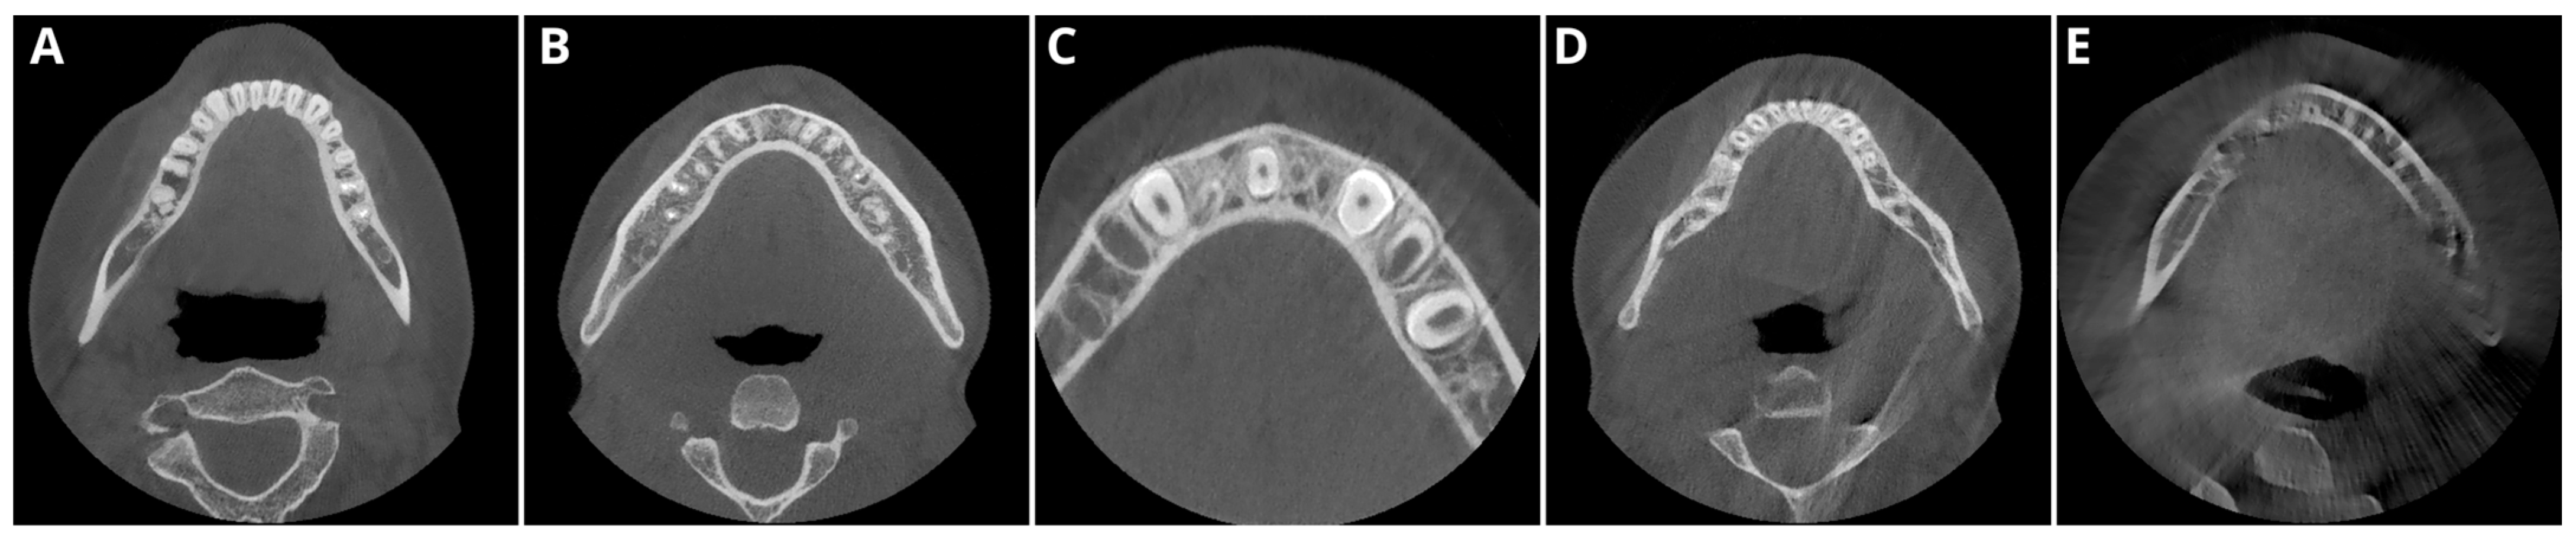

2.2. Image Acquisition and Postprocessing